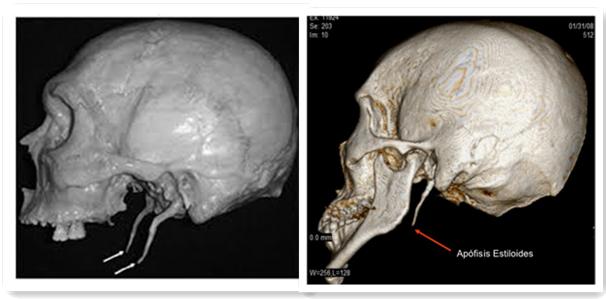

二、茎突综合征

茎突过长症又称茎突综合征,是由于茎突过长(>3cm),导致其与邻近血管、神经、肌肉等相抵触所引起的咽痛、咽异物感、吞咽不适、咽梗阻感、颈肩背部酸胀、耳痛等症状,严重者放射到耳根,尤其在吞咽时加重,部分患者可并发头痛、颈痛、反射性耳痛、流涎、失眠、耳鸣等神经衰弱的表现,患者有较重的心理负担。

该病在临床上容易被误诊、误治。扁桃体触诊,是茎突综合征诊断的最重要依据。临床上应该认真分析病史、症状,详细检查以减少误诊误治。

茎突综合征治疗有多种方法,包括外科手术治疗和针灸、颈部按摩、颈上神经节封闭、口服抗癫痫药物等治疗。茎突综合征一经确诊,症状明显者,应以外科手术切除为主。因为茎突截短后即可消除过长的茎突对神经和肌肉的刺激,故茎突截短术治疗茎突综合征的疗效是确切的。

目前茎突截短术主要有口咽径路和颈外径路两种。因为大多数患者要求手术治疗在消除症状的同时也要求美容效果。如果采取颈外径路,术后均有疤痕遗留,不利于美容,故我们大多采用口内径路截除过长茎突,所以患者均能接受且常作此要求。

经口内径路作该手术有操作不便的缺点,且茎突周围有颈内外动脉走行,术中操作应更加谨慎、轻柔,以减少术后瘢痕和炎性水肿的形成。